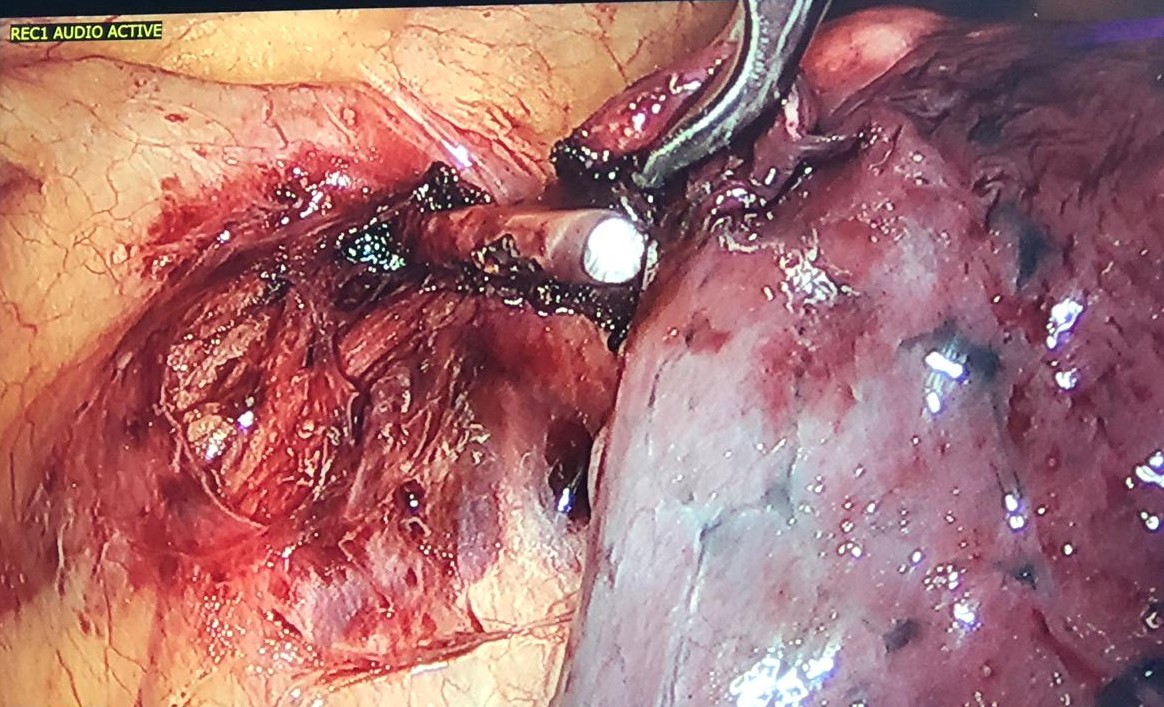

Figure 6. K-wire completely dissected from the lung. One can observe the phrenic nerve very close to the K-wire.

Figure 7. With the aid of an energy device, the authors dissected the tissues around the foreign body, in front of the phrenic nerve like in a thymectomy, and the K-wire was easily removed. It was not hooked to the left brachiocephalic vein.

The surgical approach to removing the foreign body depends on its anatomic location. Sternotomy, thoracotomy, or preferably thoracoscopy have been successfully used (4). Martins and colleagues (5) reported a 50-year-old woman who had a left humerus fracture fixed with K-wires. Sixteen years later, a chest CT demonstrated that one of the wires had migrated to the left lung. The K-wire was successfully removed by a VATS approach.

Figure 8. Extracted K-wire with its distal end bent over to avoid migration measuring approximately 5 cm.

In the case discussed here, a left VATS approach with a single lumen endotracheal tube and CO2 insufflation was used. The surgical team was prepared for a sternotomy if necessary. Another surgical strategy discussed was to remove the K-wire through a cervicotomy like in a transcervical thymectomy, using the Cooper’s sternal retractor and simultaneous videothoracoscopic control, which would allow the authors a good visualization of the brachiocephalic trunk and innominate vein, since encroaching on these vascular structures was a concern. In addition, through the cervicotomy, a partial sternotomy could be easily performed if necessary. The final decision was to start with videothoracoscopy with sternotomy capability arranged.